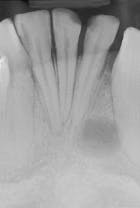

Case 1

Mesiodens